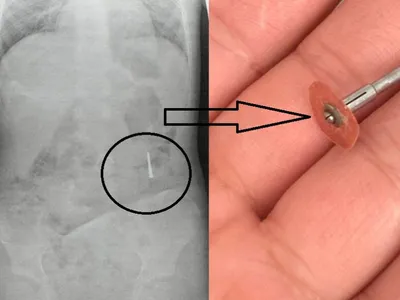

Incident grav într-un cabinet stomatologic: freză metalică scăpată în gura unui copil

Incident stomatologic grav, copil la urgențe. Un copil de 5 ani din Iași a ajuns la spital după ce a înghițit o freză metalică în timpul unei consultații stomatologice. Incident stomatologic grav, copil la urgențe Incidentul a avut loc în cabinetul unui dentist, care le-ar fi spus părinților că micuțul a înghițit doar o hârtie abrazivă, ce urma să fie eliminată fără probleme. Citește și: După ce PSD a trimis la CCR un ex-tablagiu, Nicușor Dan a nominalizat un universitar fără pată Îngrijorați, părinții l-au dus la Spitalul „Sf. Maria”, unde radiografia a arătat prezența unui obiect metalic de peste 2 centimetri. Familia susține că este vorba despre o freză dentară scăpată accidental în timpul tratamentului. Continuarea, în Ziarul de Iași